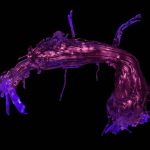

MicroRNA scaffold cancer therapy

Short genetic sequences called microRNAs, which control the proper function and growth of cells, are being investigated by researchers as a possible cancer therapy. However, their potential use is limited by the lack of an efficient system to deliver these microRNAs specifically to cancerous cells. Researchers at MIT have developed such a system, combining two microRNAs with a synthetic polymer to form a stable woven structure a bit like a net. This synthetic net can coat a tumor and deliver the two microRNAs locally to cancer cells. The two microRNAs used have different mechanisms of action and work together as a two-pronged attack: one is a tumor suppressor, and the other is an anti-microRNA, meaning that it prevents a mutated, tumor-promoting microRNA from functioning. This therapy has already been tested in mouse models of breast cancer, where it caused a tumor to shrink by nearly 90 percent after just two weeks.

JOÃO CONDE, NURIA OLIVA AND NATALIE ARTZI, MASSACHUSETTS INSTITUTE OF TECHNOLOGY (MIT)